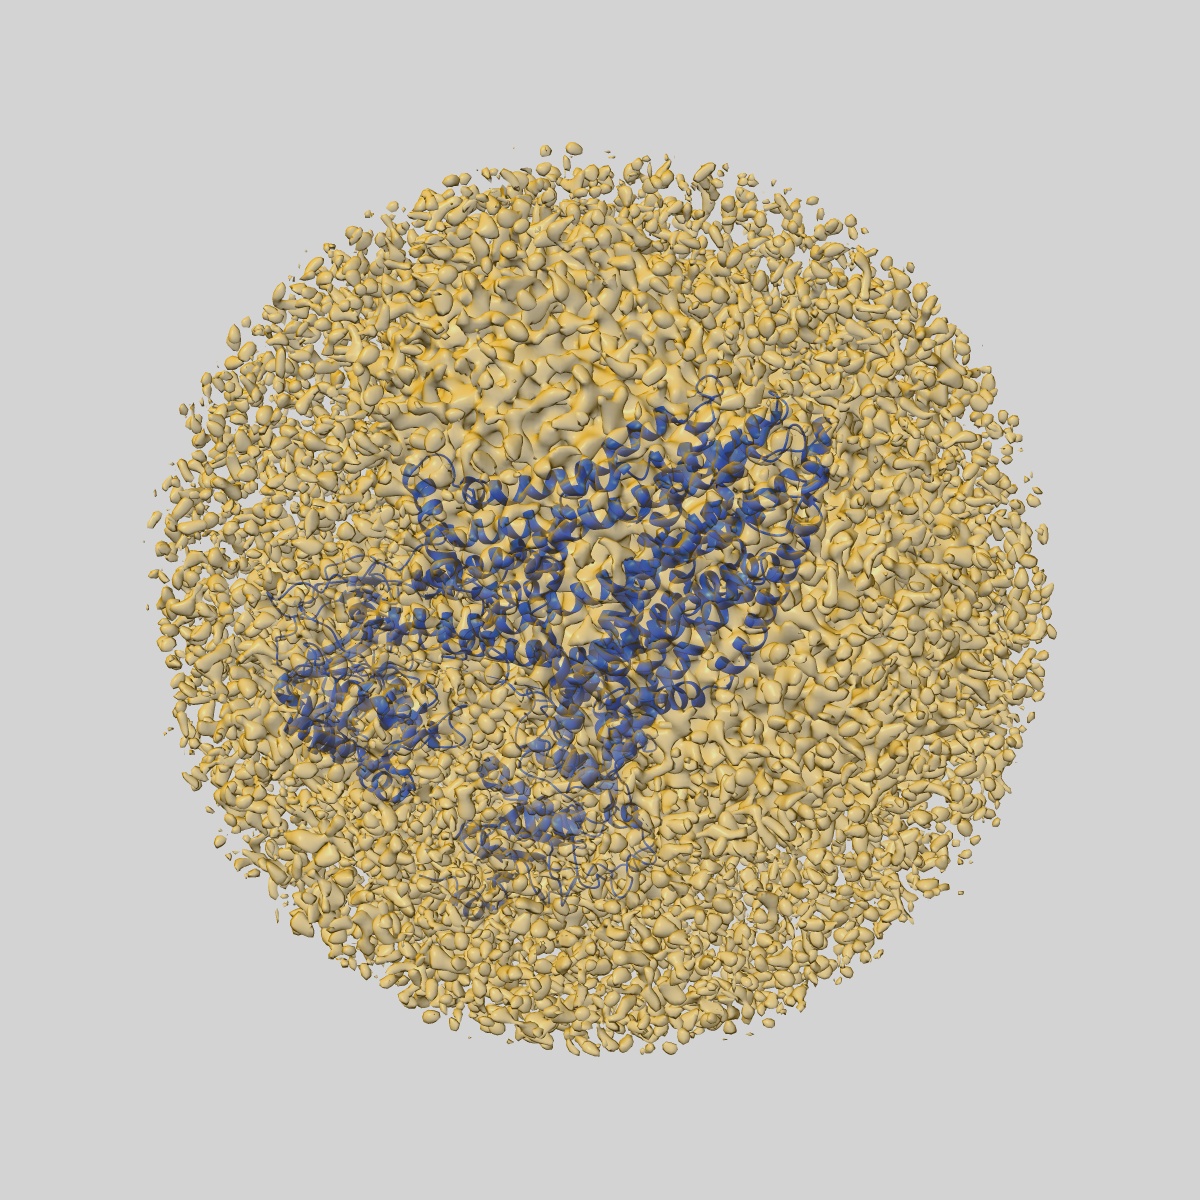

Structure of the cystic fibrosis transmembrane conductance regulator (CFTR) from zebrafish

Sample Organism: Danio rerio

Sample: Cystic fibrosis transmembrane conductance regulator or ABCC7

Fitted models: 5uar

Deposition Authors: Zhang Z, Chen J

Atomic structure of the cystic fibrosis transmembrane conductance regulator

Zhang Z, Chen J

(2016) Cell , 167 , 1586 - 1597

DOI: doi:10.1016/j.cell.2016.11.014